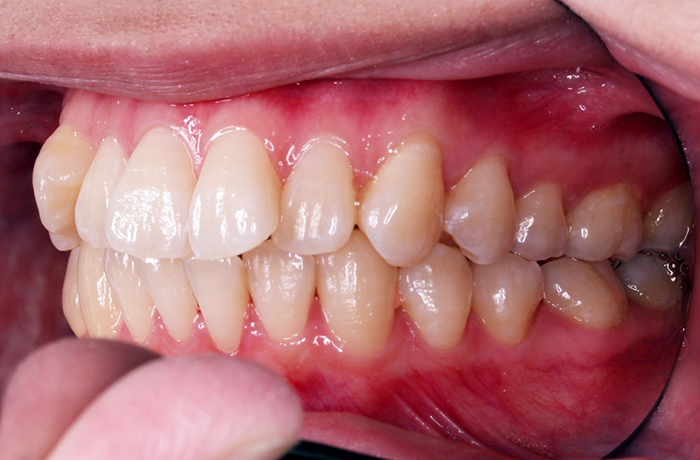

治療前

before

年齢 24歳

性別 女性

治療名称 マウスピース型カスタムメイド矯正歯科装置(インビザライン)・コンプリヘンシブパッケージ(フルパッケージ)

総額治療費用 770,000円(税込10%) 金額備考 精密検査料・診断料 33,000円(税込10%)

治療期間 10か月 通院頻度など 1か月ごと

患者の症状 上顎前歯の前突、開咬、下顎前歯部の空隙

治療方法 非抜歯で、マウスピース型カスタムメイド矯正歯科装置による矯正

上顎臼歯の遠心移動とIPR(歯間隣接面を削合)しました。

治療結果 上顎前歯の前突、開咬が改善されました。

その他治療に関する情報 顎間ゴムの使用を24時間指示しました。

リスク/副作用 1日22時間以上、装置の装着と顎間ゴムの使用が必要です。